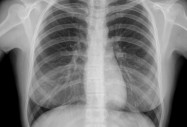

Пневмонията – инфекцията, която нарушава нормалния процес на дишане

Нови методи на лечение удължават живота при рак на белия дроб